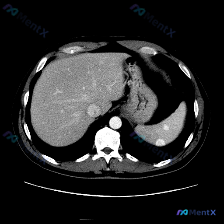

今天整理了一个很有警示意义的腹部CT病例,先看影像表现,再聊我的分析思路。 先看影像核心发现 这是一份腹部CT轴位图像: - 肝脏:实质密度均匀,血管走行正常,未见局灶性占位。 - 脾脏:形态异常,脾实质内见多发、大小不等的囊性病灶,呈圆形/类圆形,边界清晰;最大病灶位于脾中部,囊壁可见明显的环形/...

最近看到一份很有警示意义的腹部增强CT资料,整理一下思路和大家分享。 先看影像核心表现 这份是上腹部增强CT横断面软组织窗,主要异常集中在肝脏和脾脏: 1. 脾脏:体积稍大,脾实质内可见多发类圆形低密度结节灶,边界清晰,部分病灶边缘可见强化,呈「靶征」或「环形强化」改变。 2. 肝脏:肝实质内也可见...